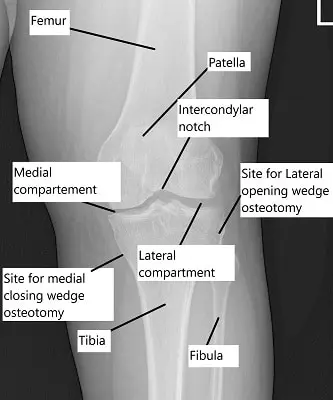

X-ray showing the knee joint

High tibial osteotomy may be classified into:

Lateral closing wedge osteotomy, where a wedge of bone is removed.

Medial opening wedge osteotomy, where the bone is opened and supported with graft.

Both methods rely on plates and screws or casts for fixation.

Types and procedure:

- Lateral Closing Wedge: A predetermined wedge of bone is removed from the upper part of the shin bone to correct the alignment. Different methods such as casts or plate and screws may be used to fix the cut ends together.

- Medial Opening Wedge: Here a cut is made on the inner side of the upper shin bone. The cut is opened up and usually filled with a bone graft. Again it may be fixed with a plate and screws.